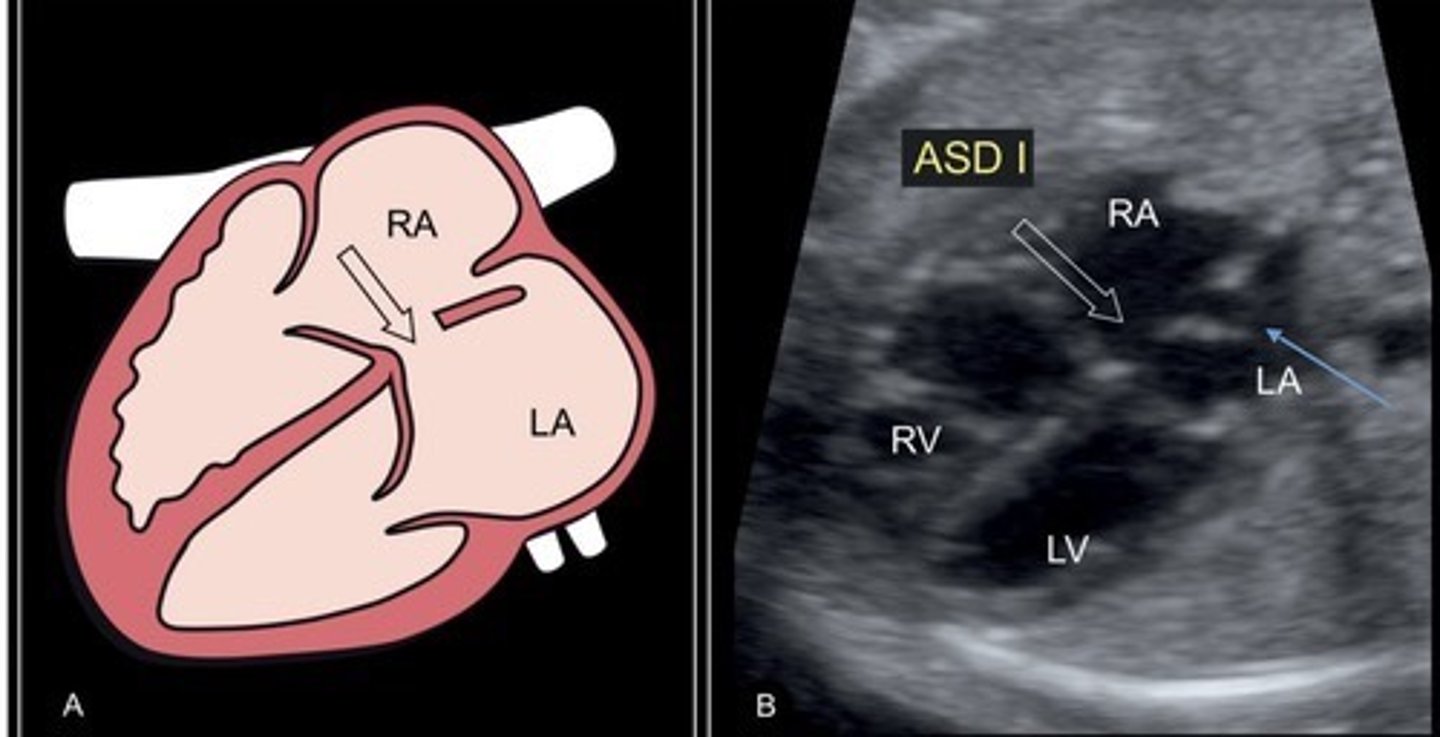

ASD

Best seen when IAS is perpendicular to sound beam

Hole in atrial septum